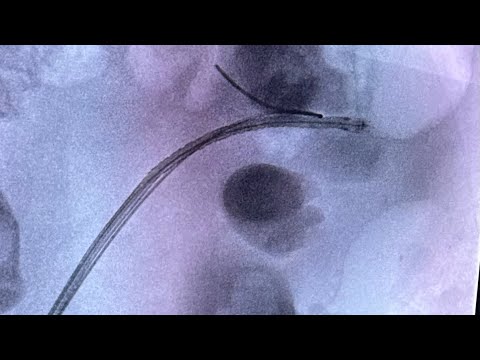

Introducing RetroPerc®: Revolutionizing Nephrostomy Creation! 🚀

Here is what Makes RetroPerc® Special?

RetroPerc - Superior Nephrostomy Creation